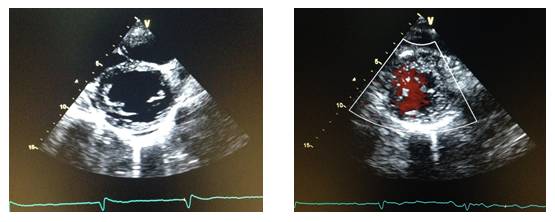

2015-9-2【心脏超声】:

二、二维超声心动图描述:

1.左房、左室增大。主动脉根部及升主动脉近端增宽

2.左室壁增厚,以室间隔增厚最明显,最厚处16-17mm。静息状态下左室壁收缩活动轻度减轻,心尖部收缩活动明显减弱,左室腔内较多疏松条索状回声。3.各心瓣膜未见明显增厚,开放不受限。

4. 心尖四腔观单平面Simpson法估计左室射血分数32%。

三、彩色多普勒超声描述:

房、室间隔水平未见明显分流。

.二尖瓣轻度反流。

.主动脉瓣中度反流。

轻度三尖瓣反流。

四、左心功能测定:

| 名称 | 测量值 | 名称 | 测量值 |

| 左室舒张末期容量(ml) | 157 | 左室收缩末期容量(ml) | 80 |

| 左室射血分数(%) | 49 | 左室短轴缩短率(%) | 25 |

| 每搏输出量(ml) | 77 |

诊断意见:

左室壁收缩活动异常,提示心肌致密化不全。

左心增大伴轻度二尖瓣关闭不全

主动脉增宽伴中度主动脉瓣关闭不全

轻度三尖瓣关闭不全

心尖切面观示静息状态下收缩活动普遍减弱;左室乳头肌水平以下,心肌组织疏松。彩色多普勒可见在疏松心肌组织中低速血流信号,窦状隐窝与心腔相通。